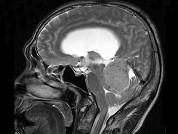

问题 男,61岁,头晕头痛伴行走不稳1月余,请根据所提供图像,选择最可能的诊断()

选项 A.胶质瘤 B.髓母细胞瘤 C.(天幕切迹缘)脑膜瘤 D.转移瘤 E.淋巴瘤

答案 C